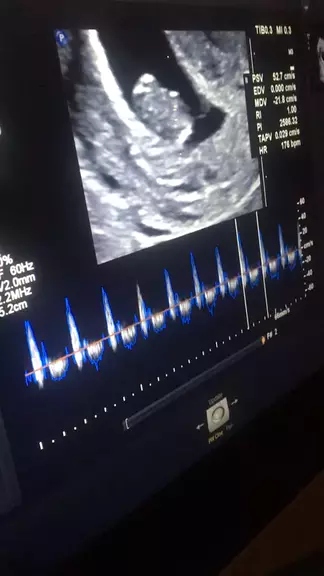

Adri.pereirah

USG Obstétrica #ultrassom #fy